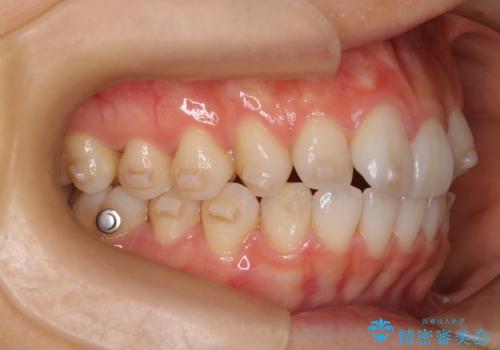

- 前歯の凸凹を主訴に来院されました。

スペースを作るために顎間ゴムを使用して、奥歯の遠心移動をおこない配列しました。

奥歯の遠心移動を行うことで、犬歯関係も良い状態に仕上げることができました。